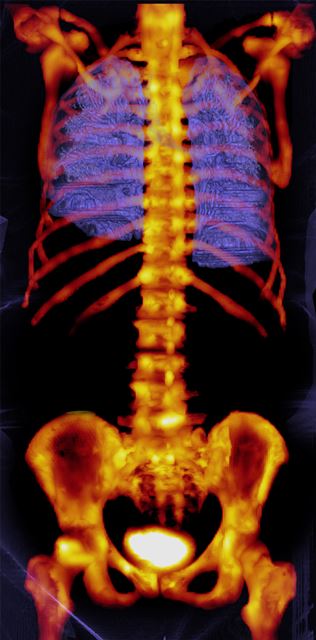

Siemens Healthcare's xSPECT system, the Symbia Intevo, combines the high sensitivity of single-photon emission computed tomography (SPECT) with the high specificity of CT to generate high resolution and, for the first time, quantitative images.

This can differentiate between tissue boundaries in bone imaging, so bone clinicians can potentially provide additional support for detection and distinguishing between cancerous lesions and degenerative disorders. The Symbia Intevo’s precise alignment of SPECT and CT provides clinicians with essential volumetric information from the CT scan, enabling accurate and consistent quantitative assessment meaning the clinician can apply quantitative information to assess whether a patient's condition has regressed, stabilised or progressed.

The Symbia Intevo from Siemens Healthcare integrates SPECT and CT enabling a high level of image quality and the ability to differentiate between tissue boundaries in bone imaging.